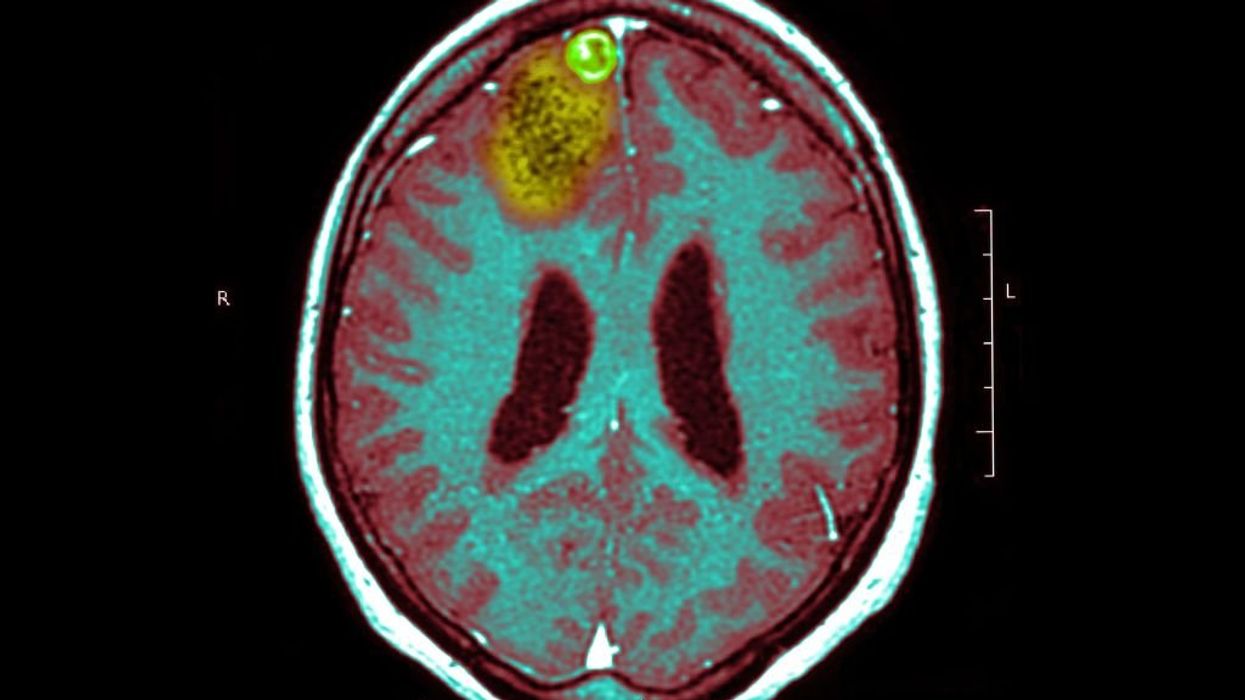

SIP/Universal Images Group via Getty Images

Richard Scolyer is a professor at Sydney University in Australia and a surgical pathologist. Professor Scolyer is also suffering from one of the deadliest forms of cancer – a glioblastoma.

The Mayo Clinic defines a glioblastoma as:

A type of cancer that starts as a growth of cells in the brain or spinal cord. It grows quickly and can invade and destroy healthy tissue. Glioblastoma forms from cells called astrocytes that support nerve cells. Glioblastoma can happen at any age. But it tends to occur more often in older adults and more often in men. Glioblastoma symptoms include headaches that keep getting worse, nausea and vomiting, blurred or double vision, and seizures.